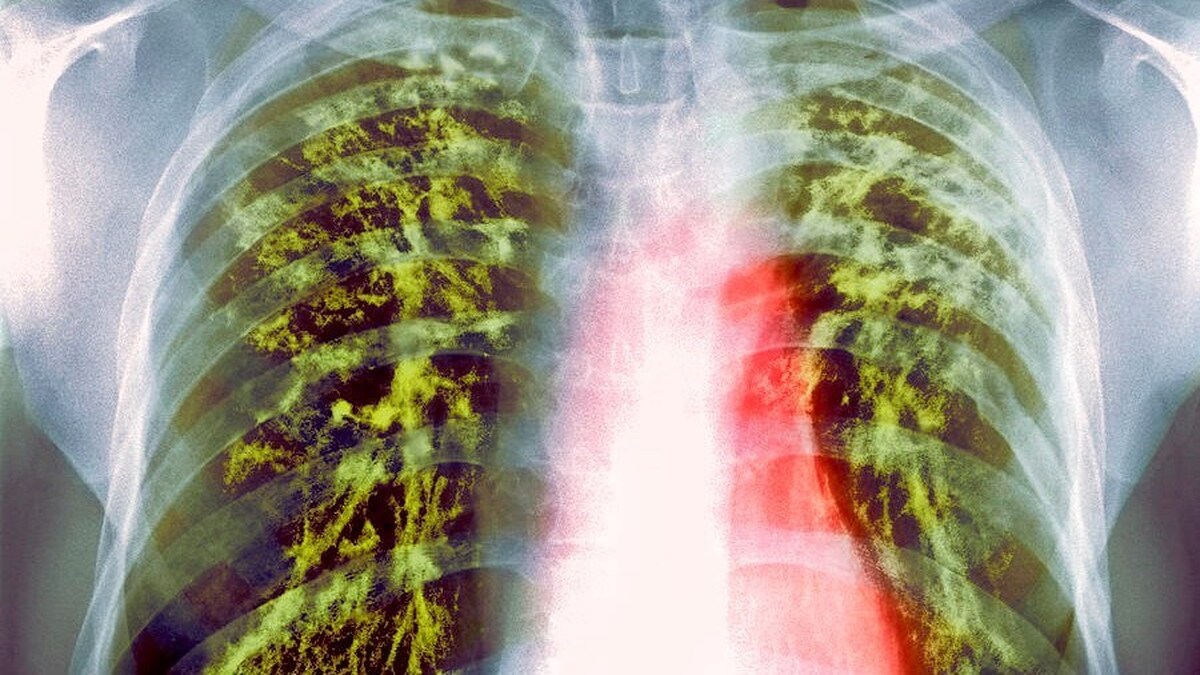

بكتيريا جديدة تساعد على علاج مرض السل المقاوم للأدوية